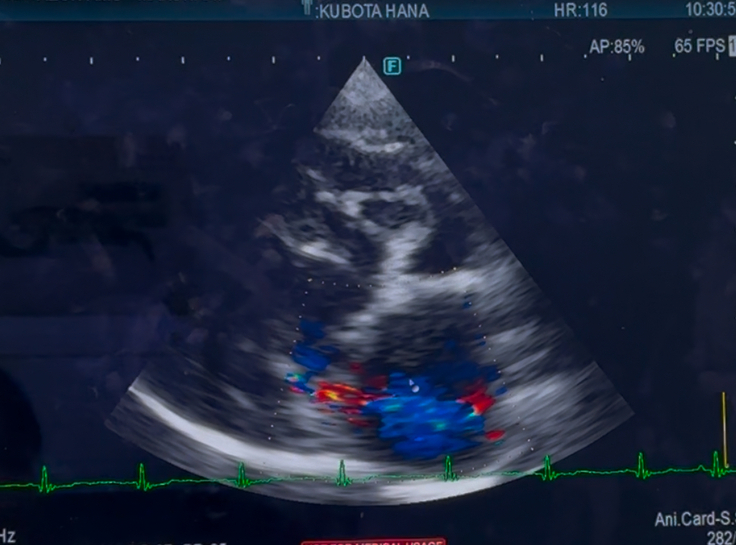

手術した、左心の方は

変わらず逆流は、あるものの

悪化はみられず、変わりなしでした

右心の、三尖弁の逆流は

少し、増えているかも…とのことでしたが

多少の、増減はあるものだと言うことと

数値より、症状があるかどうかにより

対処療法を、していくので

今現在は、咳もほとんどなく

症状は、みられないので

経過見となりました…